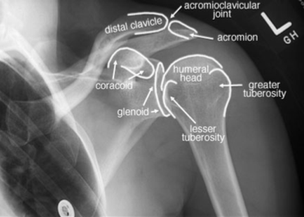

The acromioclavicular joint is formed by the AC ligament and the coracoclavicular (CC) ligament (Figure 2). The AC ligament provides horizontal stability to the joint while the CC ligaments provide vertical stability. (1)

Figure 2

Figure 2: Egol, K. A., Koval, K. J., & Zuckerman, J. D. (2010). Handbook of fractures. Lippincott Williams & Wilkins.